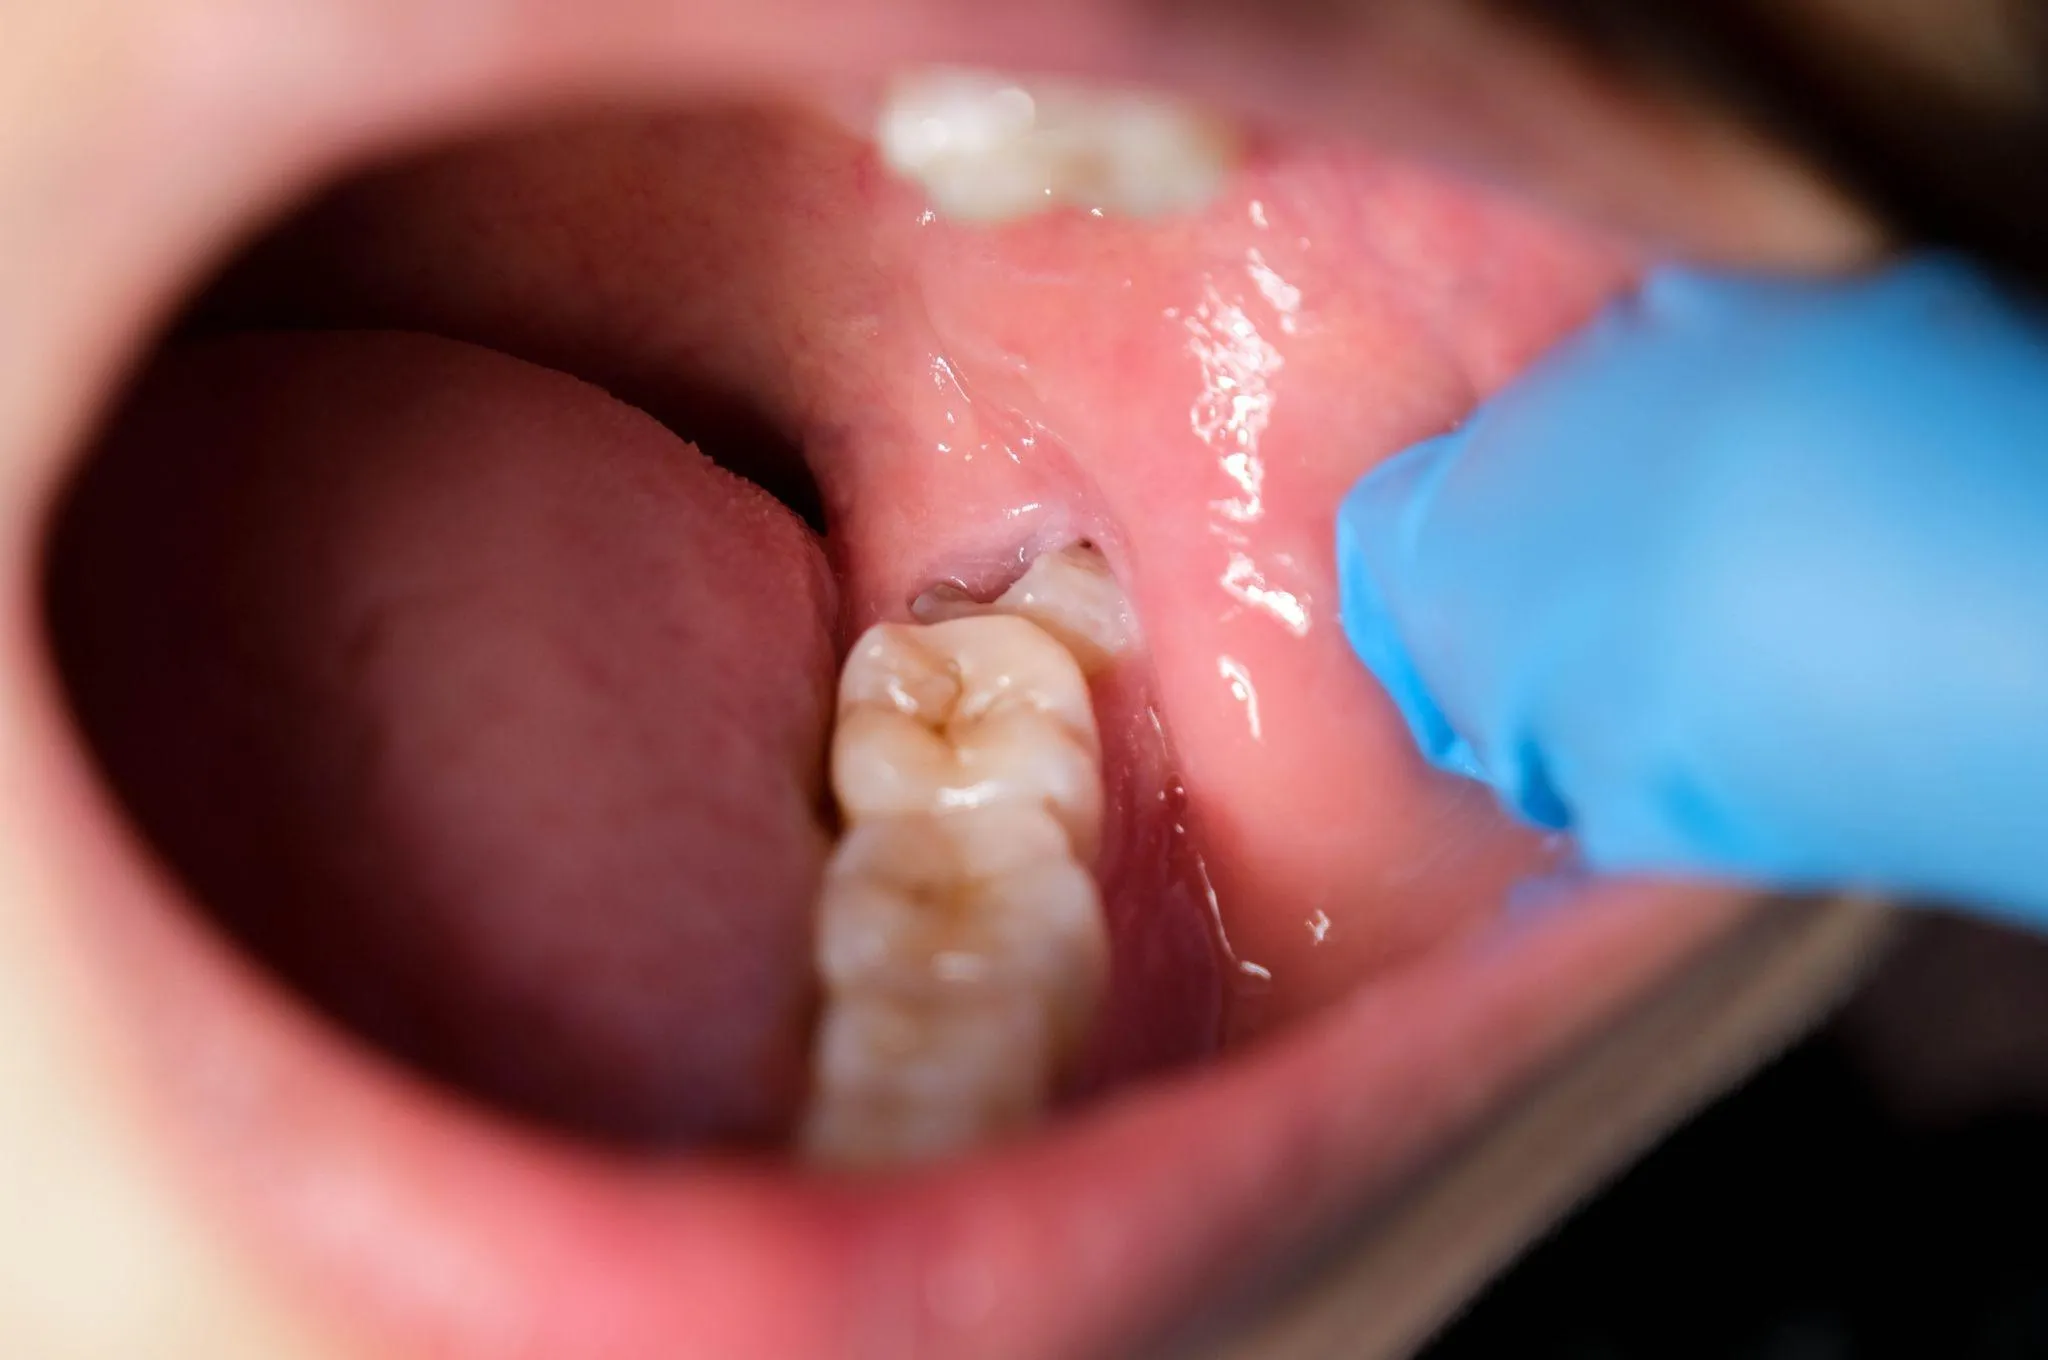

斜めに生えたり半分だけ見えていたりと、生え方に個人差が大きい点が特徴です。

生え方の影響で歯ブラシが届きにくく、汚れが溜まって虫歯や歯茎の炎症につながることもあります。

親知らずの生え方が複雑

親知らずが複雑な生え方をしている場合は、口腔外科での抜歯が勧められます。

例えば、横向きに埋まっている『水平埋伏』や斜めに生えて隣の歯を押しているケースでは、抜歯の際に骨を少し削ったり、歯を分割して取り出したりする処置が必要になることがあるのです。

また、親知らずの根の形も抜歯の難しさに影響します。

根が複数に分かれていたり、強く曲がっていたりする場合は、周りの歯や骨に負担をかけないよう慎重に歯を取り出す必要があるのです。